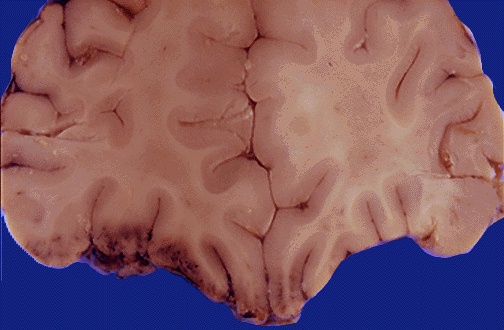

Here are less extensive contusions involving the inferior frontal lobes. The cortex shows hemorrhage and edema.